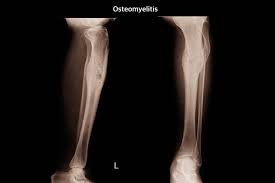

Knocheninfektion Osteomyelitis Ursachen Symptome Therapie